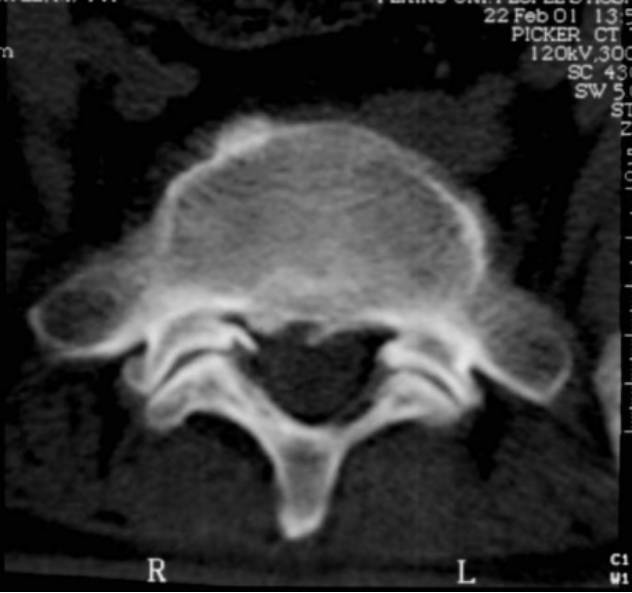

3、CT检查:可取之处在于可准确显示异常组织的性质,直接显示椎间盘突出的真实性质和范围。可清楚地显示椎管横断面的骨性结构,对侧隐窝狭窄,黄韧带肥厚,椎间关节病变及神经孔周围极外型椎间盘突出的显示有独特的临床价值。

但此检查不足之处在于对软组织分辨率低,不能直接进行矢状面、斜面扫描。对纤维环膨出显示较模糊,有假阳性情况。

椎体后方静脉孔处的骨质间隔,不要误认为后纵韧带骨化

椎管狭窄并间盘突出

椎管狭窄

中央性椎管狭窄

侧隐窝狭窄

6、腰椎管测量:在脊柱横轴CT检查中,对椎管的大小可以从五方面分析:

椎管前后径(矢状径):平均值16-17mm,下限11.5mm;

椎弓根间径(椎管横径):平均值20-30mm,下限16mm;

关节间径:L1约15(9-24)mm、L3约18(9-27)mm、L5约24(9-39)mm;

椎管面积测量:平均值2.1-2.4c㎡,下限1.45c㎡;

侧隐窝宽度:L2约13 (6-21)mm、L3约12 (6-18)mm、L4约13 (4-20)mm、L5约7 ?(2-15)mm、S1约6 ?(2-14)mm。

腰椎管测量:1、椎管前后径;2、椎弓根间径;3、椎管;4、侧隐窝宽度;5、椎板间径